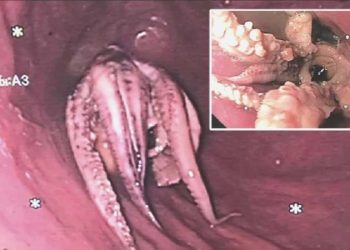

Read moreYediği yemeğin akabinde istifra şikayetiyle doktora giden adamın boğazından ahtapot çıktı.